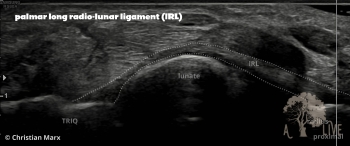

carpal ligaments